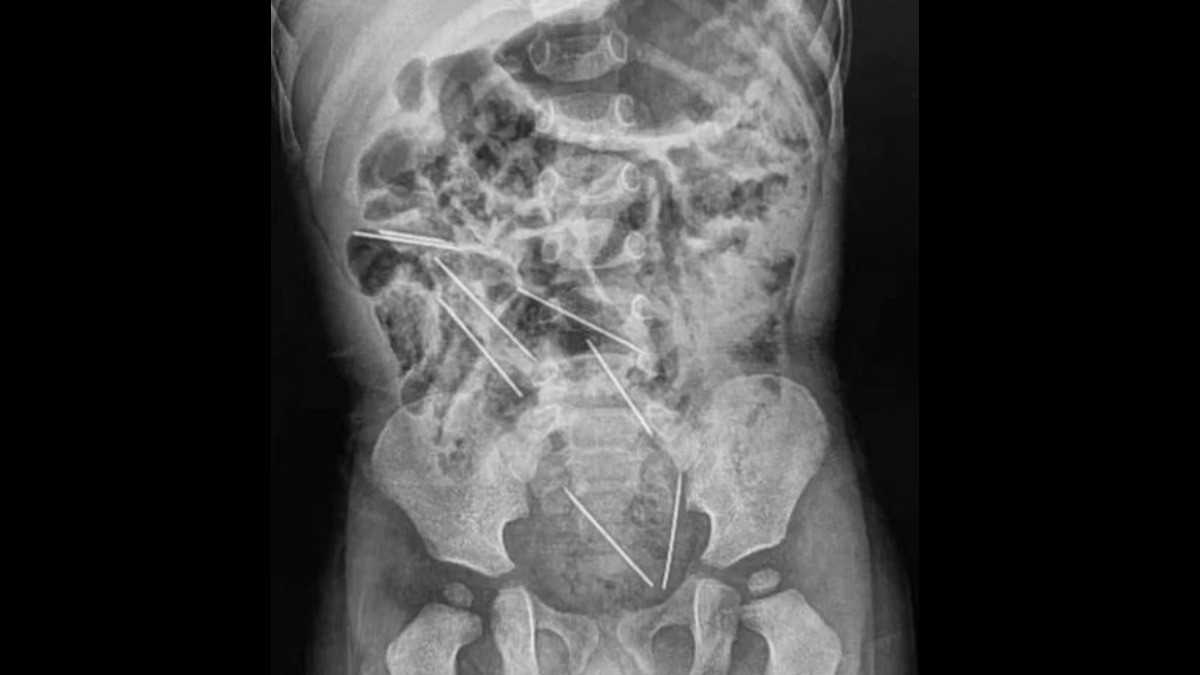

Al darse cuenta del accidente, de inmediato llevó al niño a urgencias en un hospital de Tarapoto. Cuando los médicos le realizaron una radiografía del abdomen, confirmaron que se había tragado ocho agujas.

El cirujano que encabezó la operación, dio a conocer que las agujas estaban en diferentes lugares del abdomen del niño, algunas de ellas en posiciones peligrosas. Dos agujas estaban ubicadas entre la vejiga y el recto, lo que agravaba la situación.